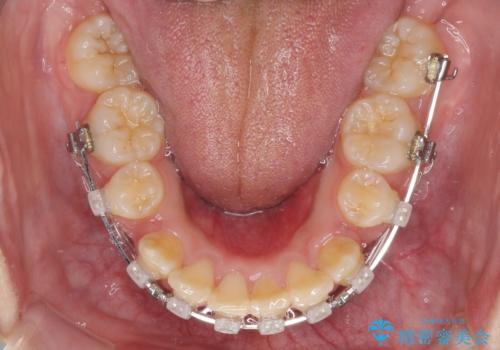

- クリアブラケット

- 2年1ヶ月

前歯部叢生のスペースを獲得するため、上下顎左右小臼歯各1歯を抜歯することとしました。